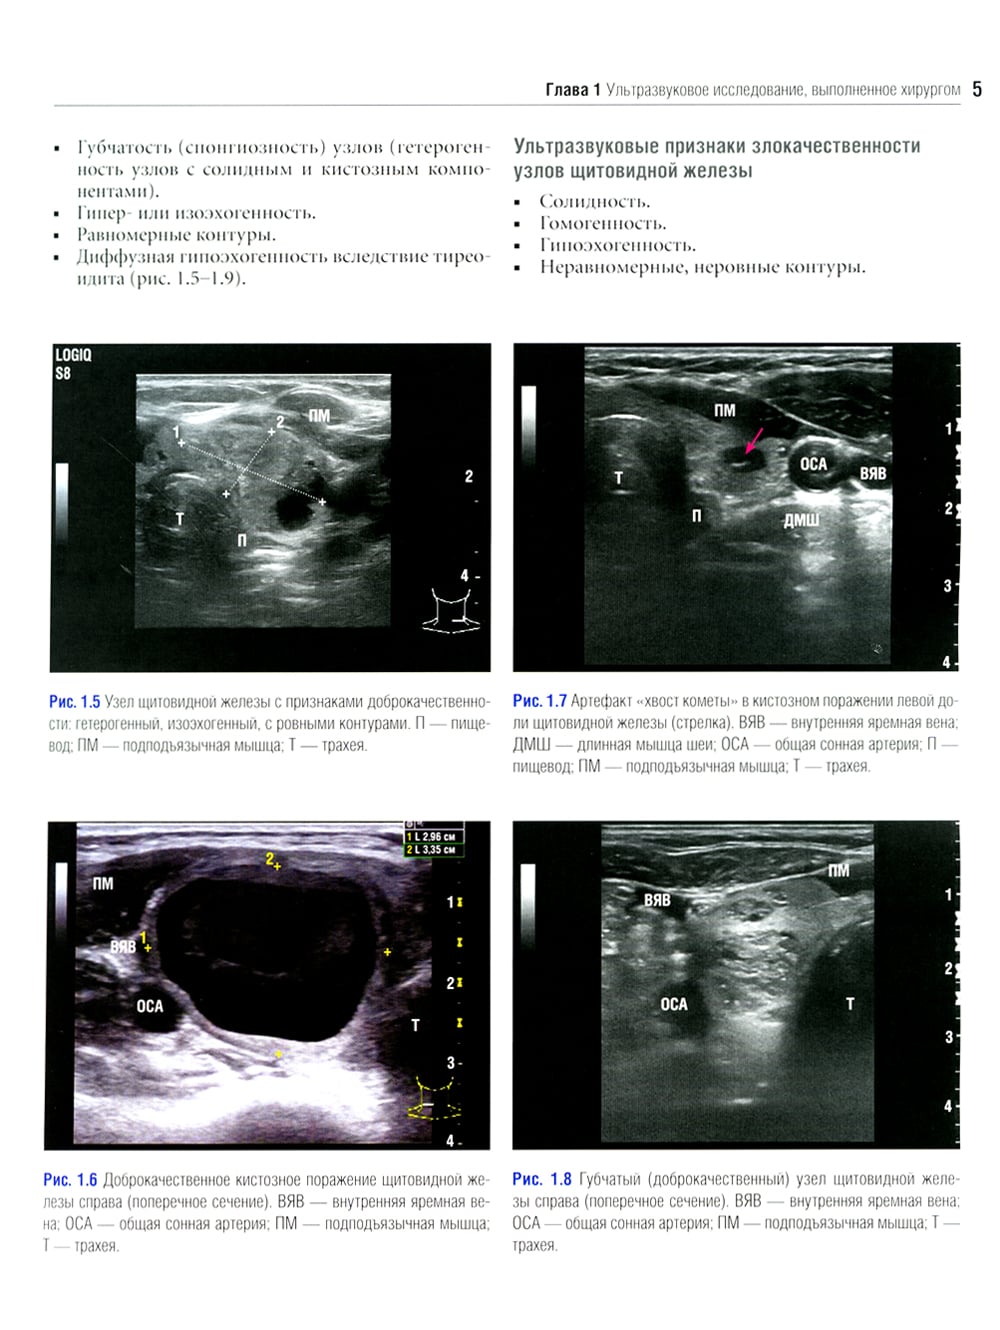

Данное издание представляет собой великолепно иллюстрированный хирургический атлас. В нем рассмотрены методы ультразвукового исследования шеи, молекулярно-генетическое тестирование пациентов с узловыми образованиями в щитовидной железе, робот-ассистированные хирургические методы, техника эндоскопических операций при эндокринных опухолях, хирургия при рецидиве заболевания, аутотранснлантация и криоконсервация околощитовидных желез, адреналэктомия при метастазе в надпочечнике, хирургия нейроэндокринных опухолей тонкой кишки и их метастазов в печени. «Атлас эндокринной хирургии» состоит из 4 частей: «Хирургия щитовидной железы», «Хирургия околощитовидных желез», «Хирургия надпочечников», «Хирургия опухолей поджелудочной железы и карциноидов». Всего в издании 29 глав, подготовленных сотрудниками экспертных факультетов ведущих медицинских школ США, Европы и Азии. Каждая глава состоит из разделов, в которых описаны общие сведения, показания и противопоказания, оценка риска, алгоритм принятия решений и планирование вмешательства, необходимое оборудование и материалы, хирургические техники, результаты лечения, осложнения и последующее наблюдение, а также даны советы и предостережения авторов. В книге много информации, которой нет в других источниках. Наряду с многочисленными фотографиями, сделанными в ходе операций, а также данными, полученными при различных методах визуализации, приведено значительное количество иллюстраций и видеоматериалов, демонстрирующих хирургическую технику или обследование. Издание предназначено практикующим врачам в области эндокринной хирургии, специалистам в смежных областях медицины и студентам медицинских высших учебных заведений.| Издательство | Логосфера |